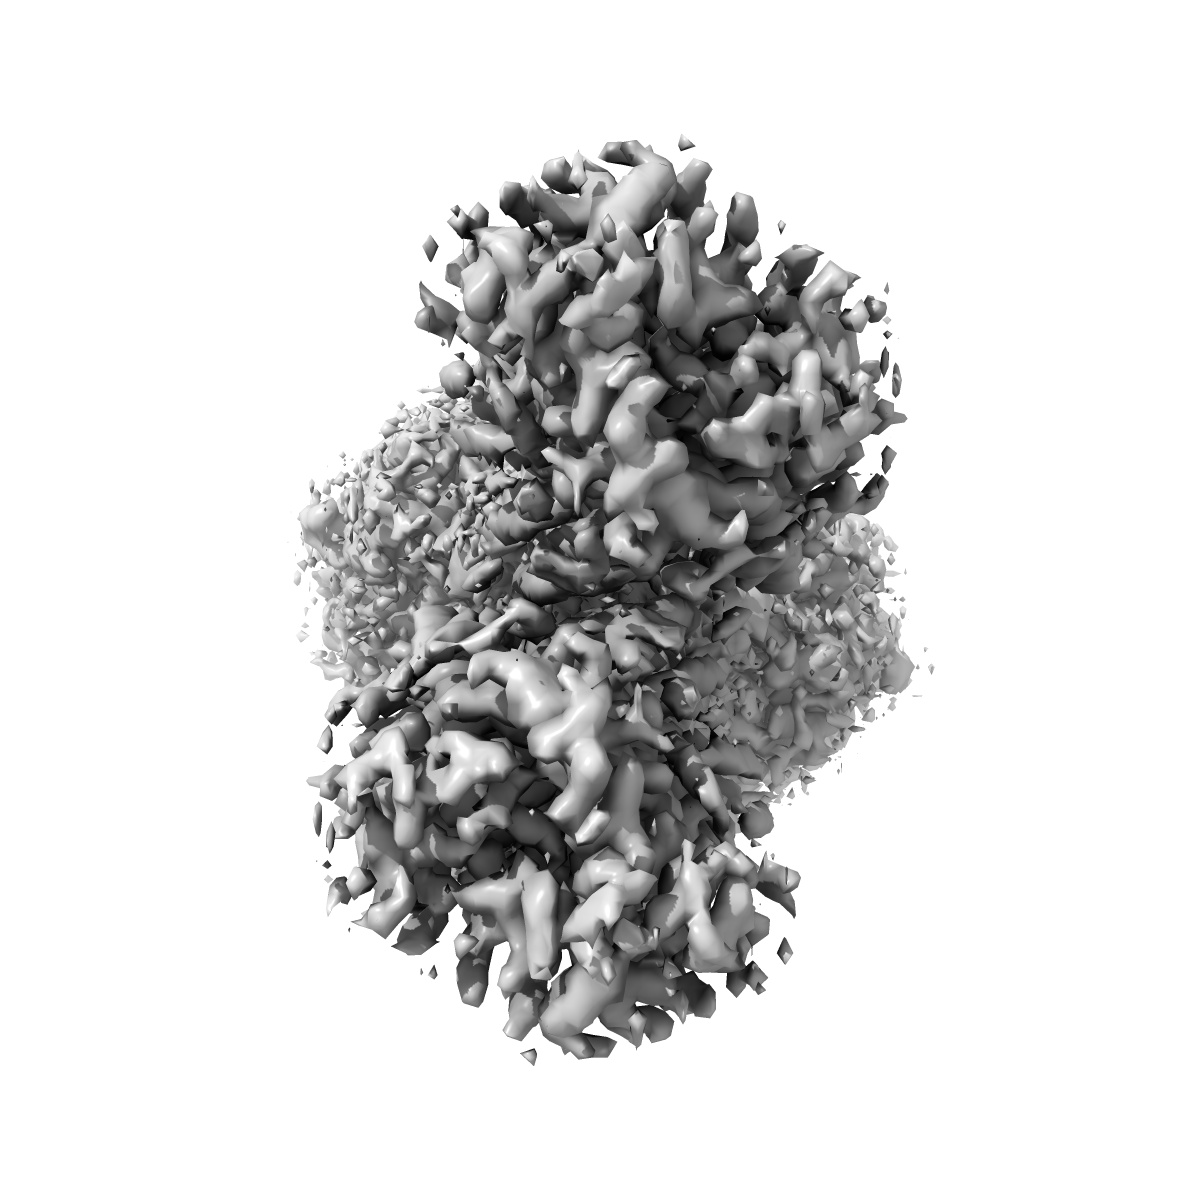

Asymmetric Activation of the Calcium Sensing Receptor Homodimer

EMD-23652

Single-particle3.2 Å

Sample: human extracellular calcium-sensing receptor complexed with negative allosteric modulator NPS-2143 under high calcium high Trp condition

Fitted models: 7m3e

Asymmetric activation of the calcium-sensing receptor homodimer.

(2021) Nature , 595 , 455 - 459